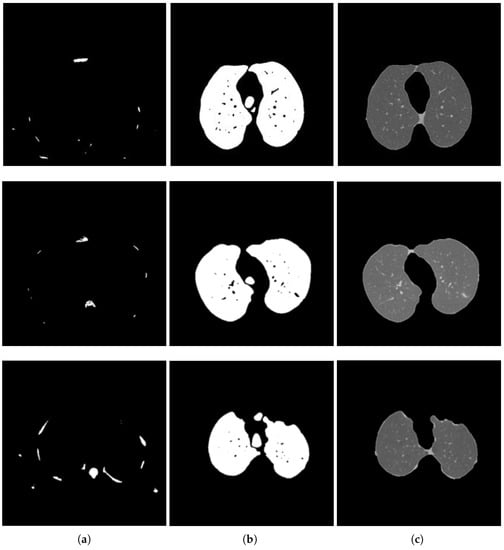

2.2.1. Segmentation in Lung Window

2.2.2. Segmentation in Mediastinal Window